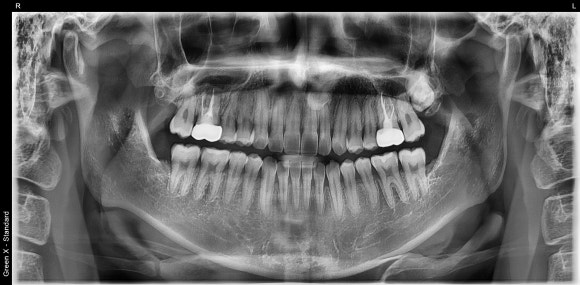

20240805

오늘 살펴볼 케이스는 20대 남성 환자분의 재신경치료입니다.

10년전에 한 치료가 왠지 모르게 불편해서

저에게 오셨습니다.